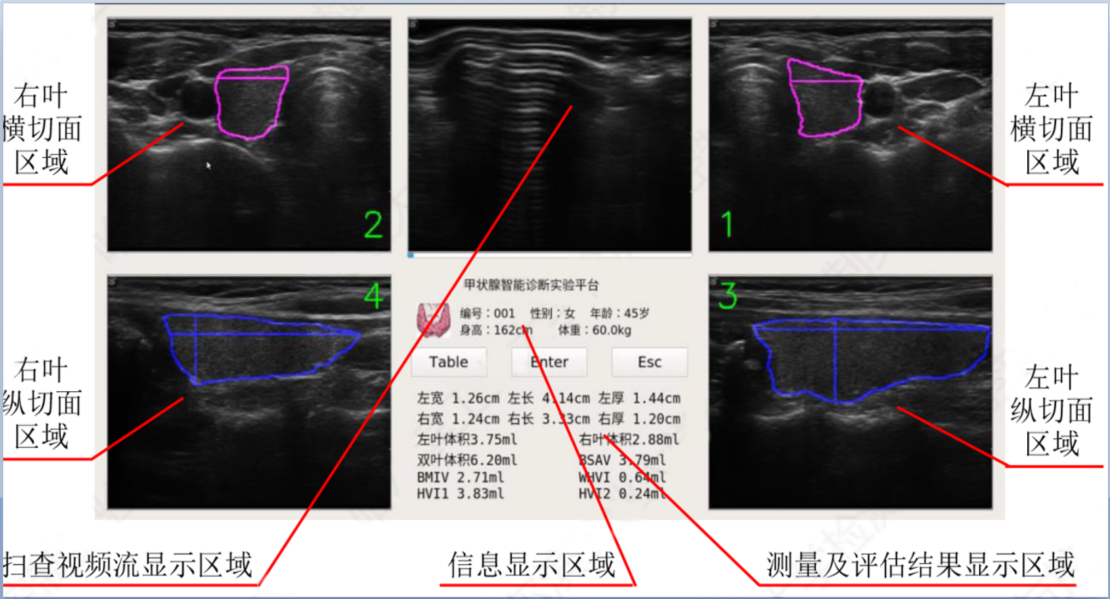

在系统主界面的扫查视频流显示区域可以看到实时变化的扫查图像,系统运用智能算法可以分别用粉色和蓝色区别标注甲状腺的横切面和纵切面并将切面的边缘勾勒在图像上,医生确认满意后即可退出智能选择切面功能。